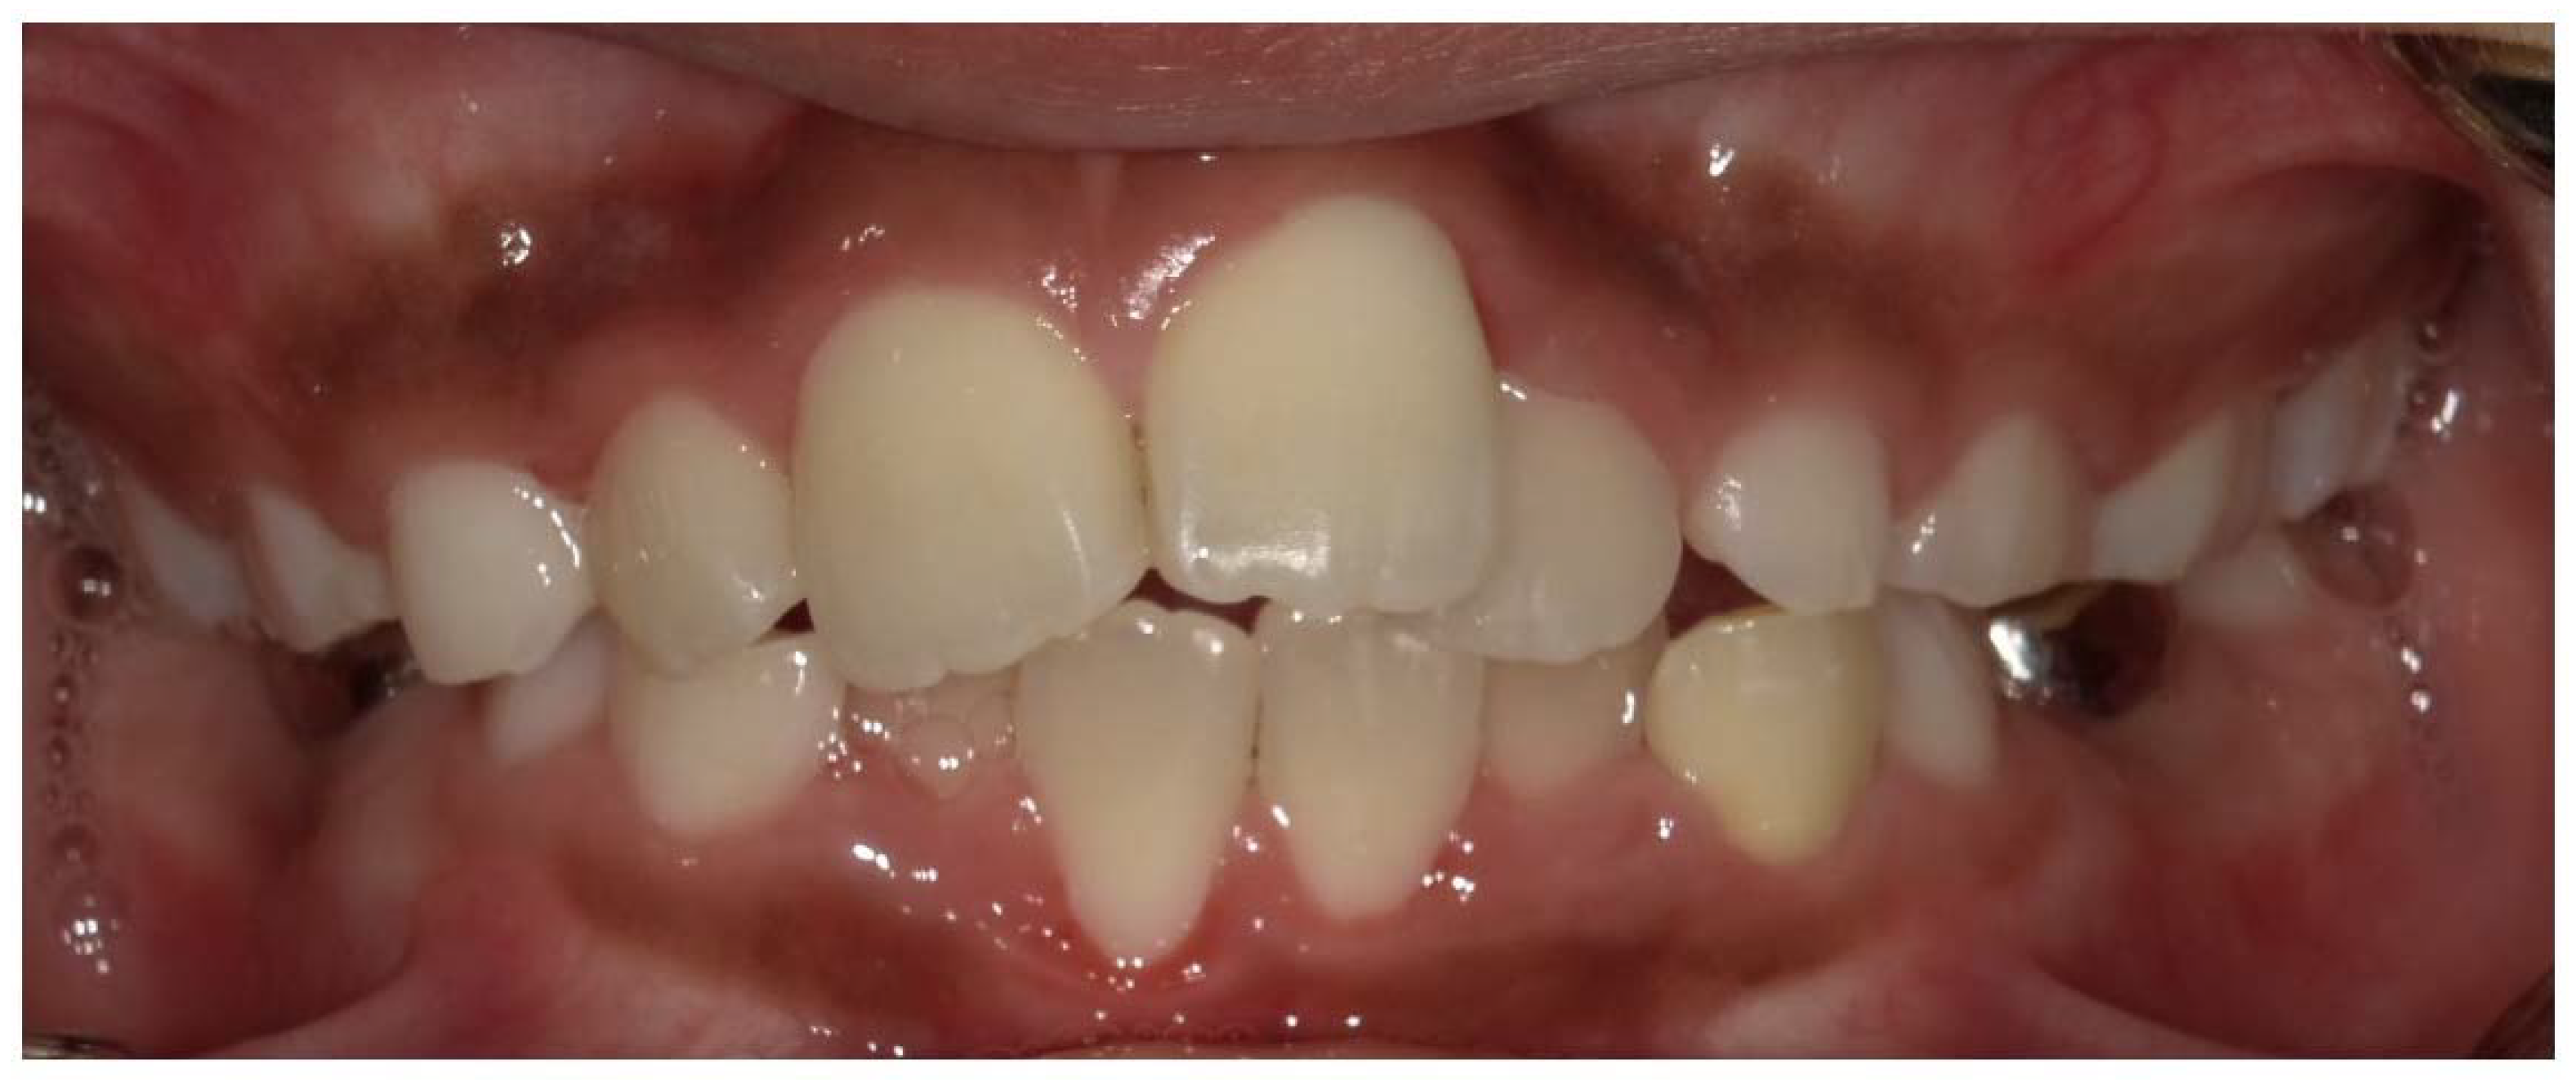

- Okawa, R.; Hamada, M.; Takagi, M.; Matayoshi, S.; Nakano, K. A Case of X-Linked Hypophosphatemic Rickets with Dentin Dysplasia in Mandibular Third Molars. Children 2022, 9, 1304. [Google Scholar] [CrossRef]